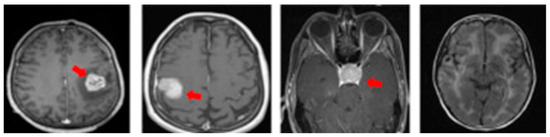

MRI also offers specialized imaging sequences that provide valuable insights into brain tumors, such as diffusion-weighted imaging (DWI), which helps differentiate tumor cells from healthy brain tissue; perfusion imaging, which assesses blood flow within the tumor to evaluate its aggressiveness; and magnetic resonance spectroscopy (MRS), which analyzes the tumor’s chemical composition to aid in diagnosis and treatment planning. For illustration purposes, Figure 2 provides a visual comparison of normal and tumorous brain MRI images with encircled areas, and Figure 3 illustrates the types of brain tumors in MRI images.

Overall, this period marks a significant transition from proof-of-concept DL models to clinically viable tools that promise to revolutionize brain tumor diagnosis while addressing key challenges in standardization and validation. Based on the literature review, it was inferred that most of the approaches are tested on a single limited-size dataset; most of the works did not detect the type of the tumor (shown in Figure 3), and few research studies addressed multiple views of MRI images (shown in Figure 2) and exploited them for progression of tumor stages and thus helped the physician plan treatment accordingly. Despite this, benchmarking and regulatory efforts accelerated to bridge the clinical translation of these efforts.

MRI scans are typically obtained in three anatomical planes—axial, coronal, and sagittal—each offering distinct views of brain structures and abnormalities, illustrated in Figure 2. Utilizing data specific to these planes in brain tumor detection and classification models allows for a comprehensive understanding of tumor characteristics. These MRI view-specific models capitalize on the strengths inherent to each anatomical plane, enhancing diagnostic precision and accuracy. Figure 3 shows these multiple-view MRI slices and brain tumor classifications.